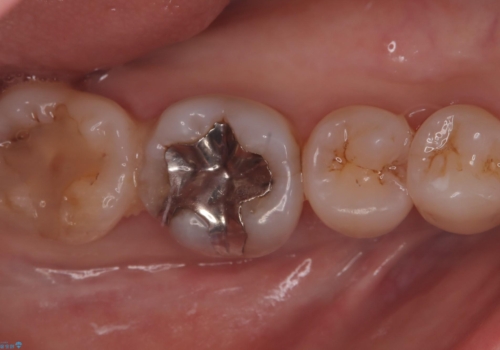

- 主訴:右下のセラミックのブリッジが何度も同じところで折れて壊れてしまう。

対合歯との咬合関係において、右下7番目と6番目の被せものの連結部がたわみやすい環境にあったため、ブリッジの新製ではなくインプラント治療を行いすべての歯を単冠仕上げとすることにしました。

何度も右下6、7間でブリッジが折れてしまうとのことでした。対合歯とブリッジの連結部が強く当たりたわみやすい状態でした。破折しずらい金属を使用したブリッジの選択もありましたが、支台歯(右下7)が失活歯場合、破折リスクが高く、破折してしまった場合にまたブリッジを外しての再治療になってしまう可能性を説明したところ、全て単冠仕上げとできるインプラント治療を希望されました。

右下5番のクラウンは、ブリッジを切断しそのまま使用していただいています。